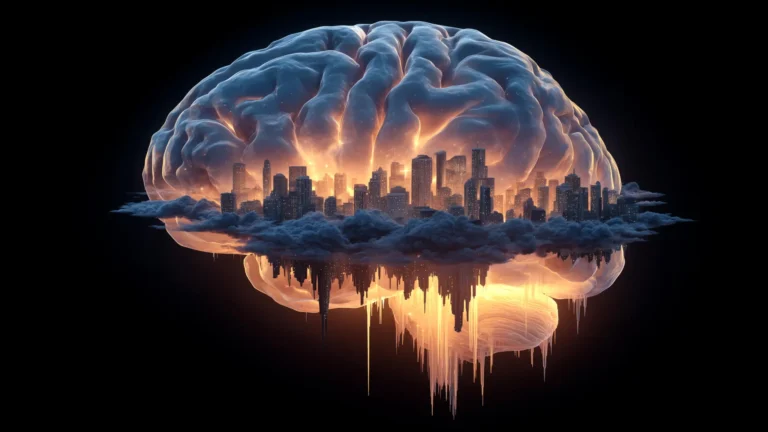

To rigorously ascertain the causal relationship between elevated BMI and dementia, the research team employed a sophisticated analytical framework known as Mendelian randomization. This study design, often likened to a natural experiment that mimics the controlled conditions of a randomized controlled trial, leverages common genetic variations associated with higher BMI. These genetic predispositions act as proxies for pharmacological interventions that might alter BMI. In a typical drug trial, participants are randomly allocated to receive either an active therapeutic agent or a placebo, thereby isolating the drug’s effect. Similarly, Mendelian randomization capitalizes on the random inheritance of genetic variants from parents to offspring. These variants either predispose an individual to a higher BMI or do not. The inherent randomness of genetic inheritance ensures that the distribution of these BMI-influencing genetic variants is largely independent of other lifestyle or environmental factors that could confound the results. By observing the health outcomes in individuals with different genetic endowments for BMI, researchers can infer the causal impact of BMI on disease development without the typical confounding variables often encountered in observational studies. This powerful technique enabled the researchers to distinguish cause from effect, clearly identifying high BMI as a direct determinant of increased dementia risk.